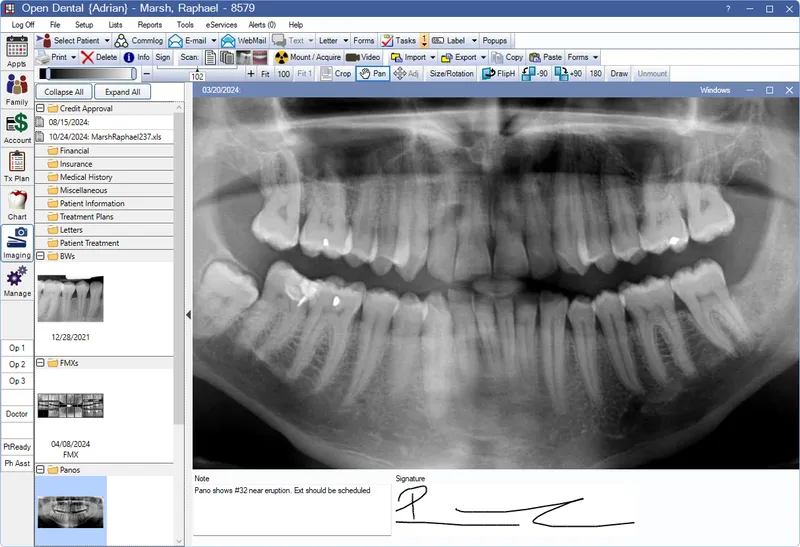

- Radiographs (X-rays): IOPA, OPG, Bitewings

- Core Principle: Comparison of ante-mortem (AM) and post-mortem (PM) radiographs.

- IOPA (Intraoral Periapical), OPG (Orthopantomogram), Bitewing.

- Tooth & root morphology, pulp anatomy.

- Restorations: type, material, shape.

- Bone trabeculation, sinus patterns (e.g., maxillary).

- Pathology, anomalies, implants, foreign bodies.

- Comparative Dental Identification: Matching ante-mortem (AM) with post-mortem (PM) records. Key for positive ID.